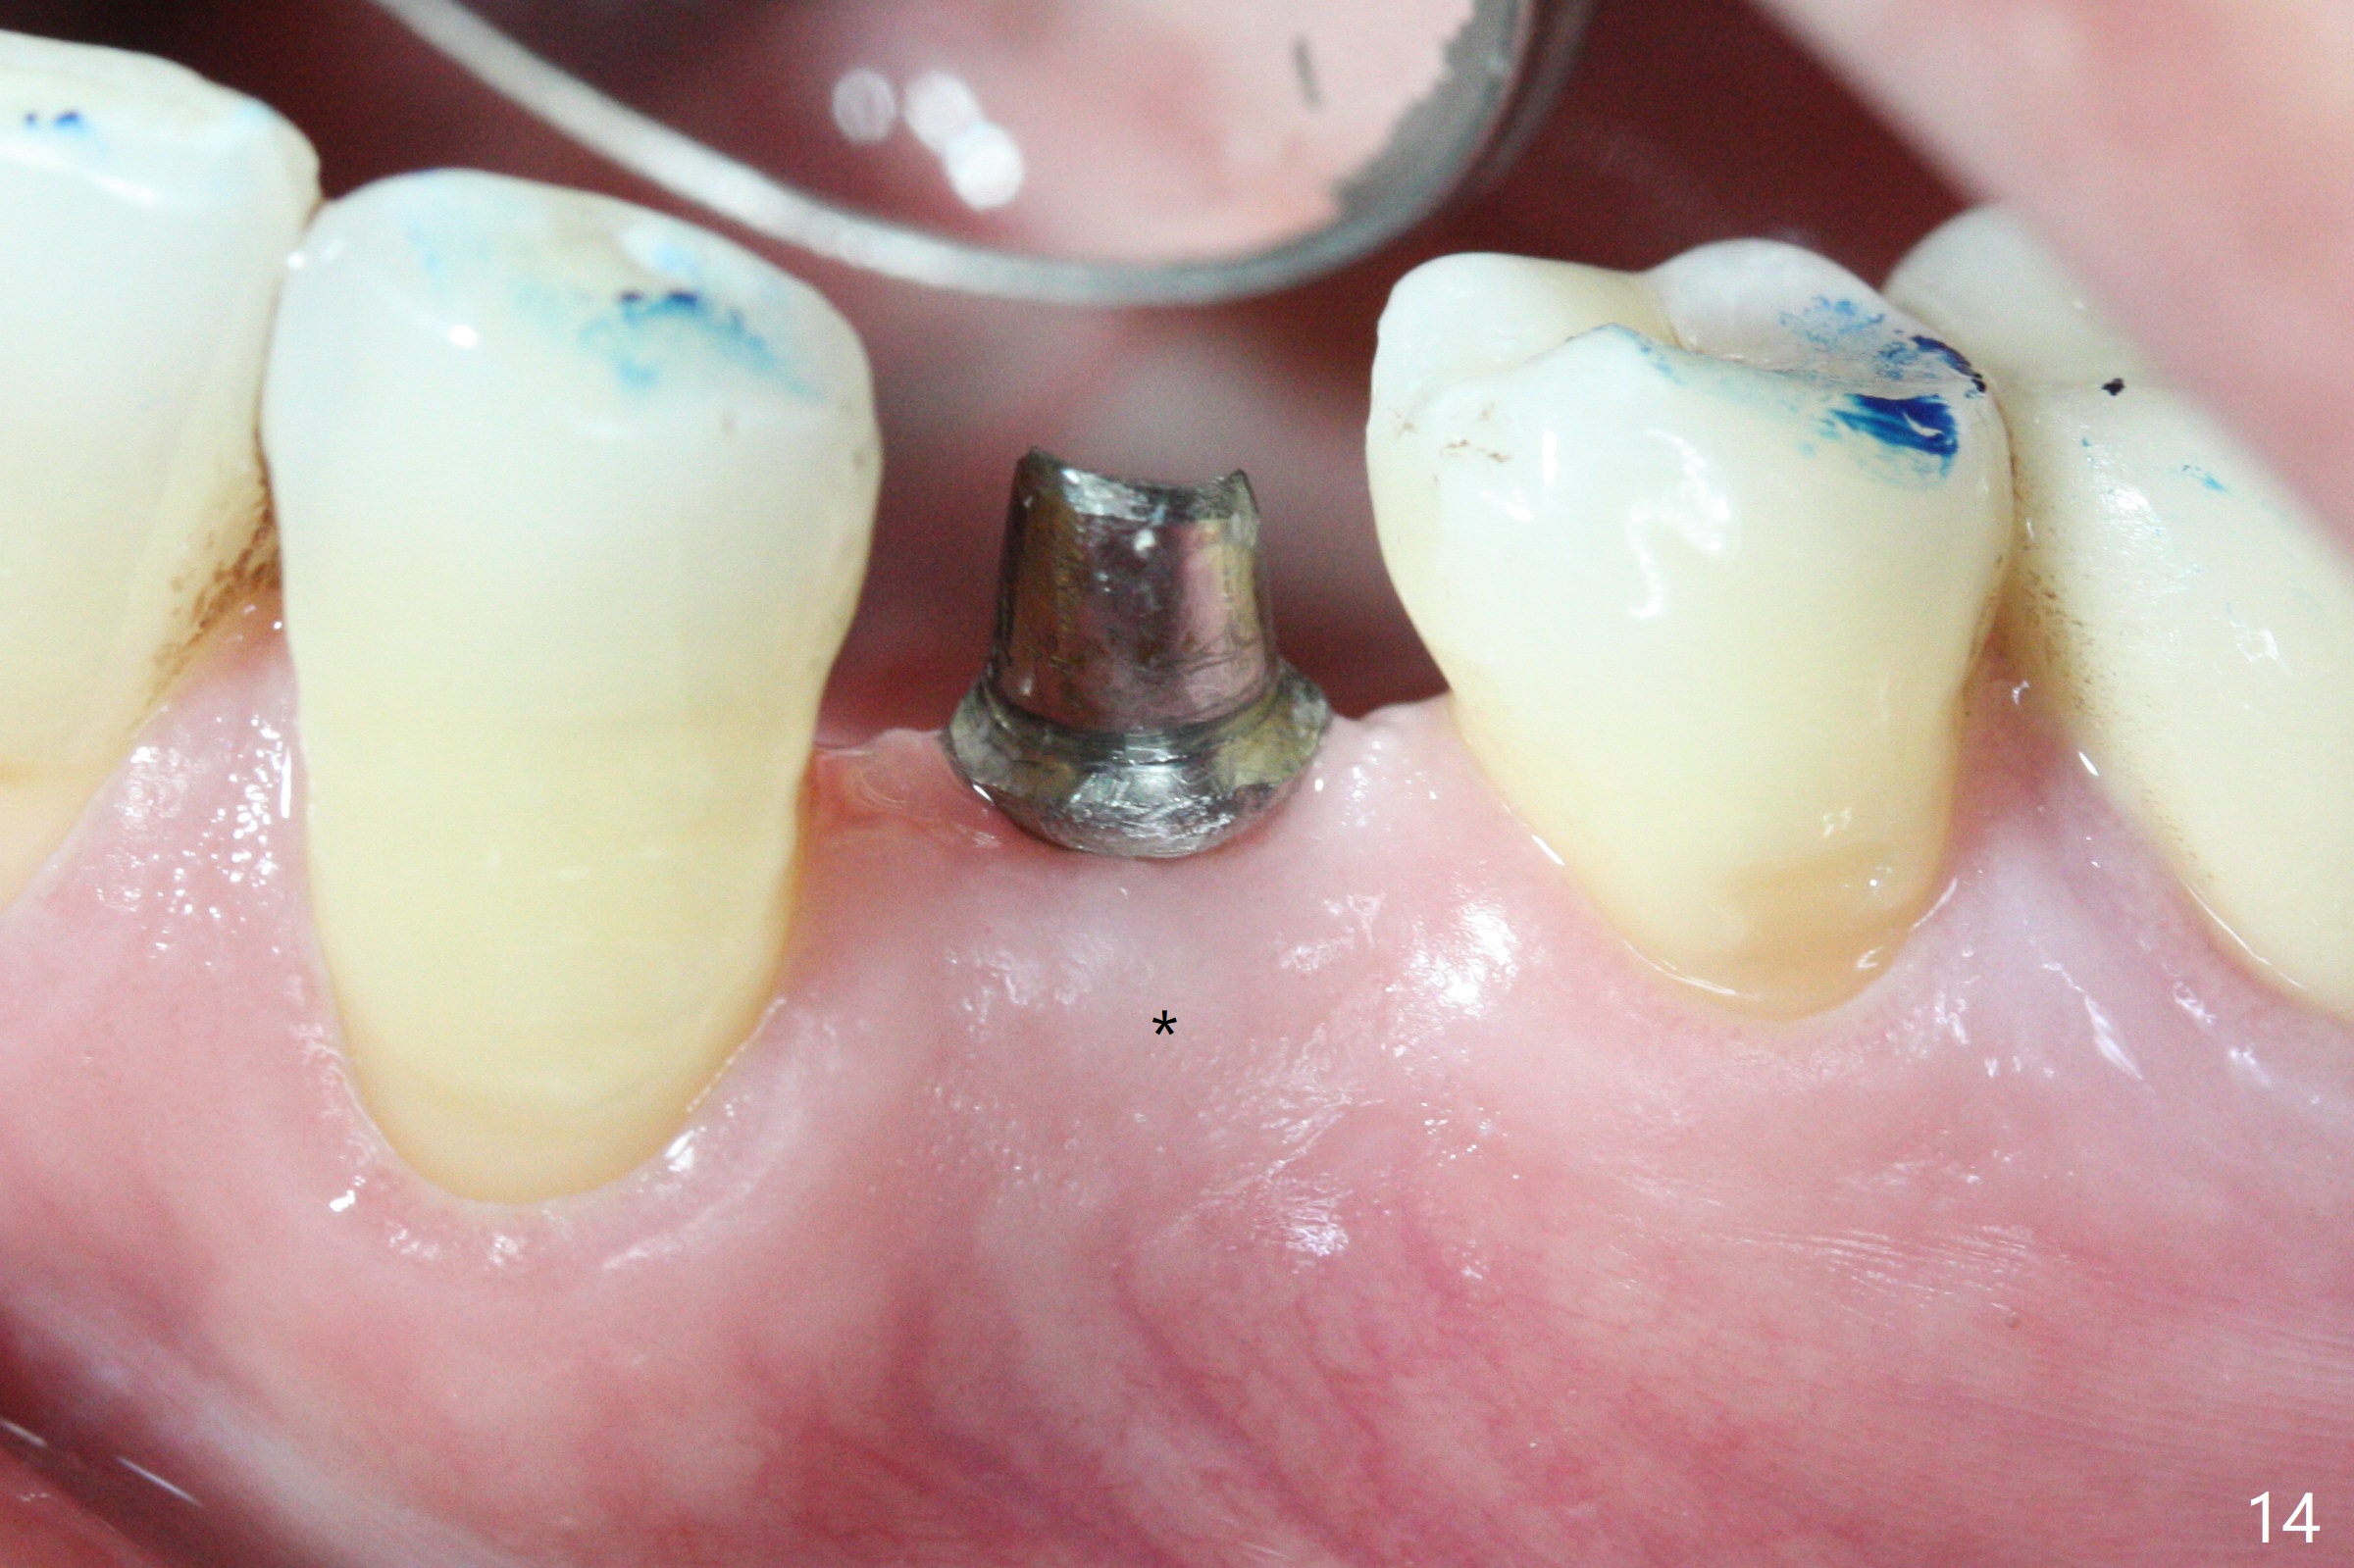

The implant seems to have osteointegrated 4 months postop (Fig.9). When a permanent crown is fabricated, it should have normal occlusal and buccal contour (from Fig.11 (provisional) to 12 red and black curved lines) as well as the buccal cervical extension (Fig.12 to cover the buccal gingiva (Fig.10 *). If the lingual margin of the abutment is too prominent, return the case and the abutment will be changed to the one with 2 mm cuff (existing 3 mm). The lingual margin of the abutment will be trimmed. The patient is not pleased with the short buccal margin of the crown after cementation (Fig.13). In fact the provisional should have been fabricated so that the its buccal margin should be subgingival and within the gingival outline. It may prevent buccal plate collapse. In fact the crown dislodges 1 year post cementation. The lingual margin is prep lower to increase the abutment height. Impression is taken. Although the access hole is unnecessary for cementation, it acts as an escape hole so that there is no excess cement cervically (Fig.14-18).